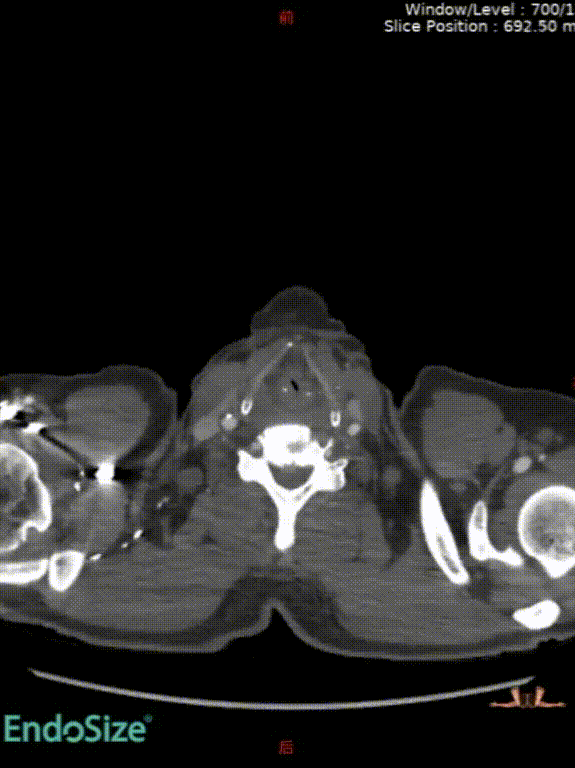

术前情况:74岁男性,肾下腹主动脉瘤,瘤体最大直径66mm,累及双侧髂总,右侧髂内扩张伴开口狭窄,左侧髂内夹层。

手术过程:根据患者及家属要求保双侧髂内,遂计划双侧髂内重建,右侧优先,左侧髂内情况尝试开通。手术中,先进行造影和翻山建立通路。